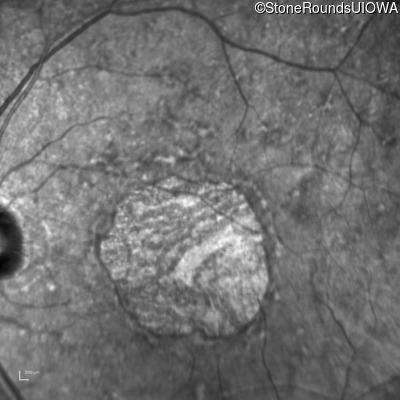

Pattern Dystrophy (IIC)

Age at visit: 47 years

This 47 year man first experienced some decrease in his central vision about 10 years ago.

Diagnosis & molecular findings

Disease Gene Allele 1 variant(s) Allele 2 variant(s) Inheritance mode

Pattern Dystrophy PRPH2 Gly167Asp GGC>GAC   AD